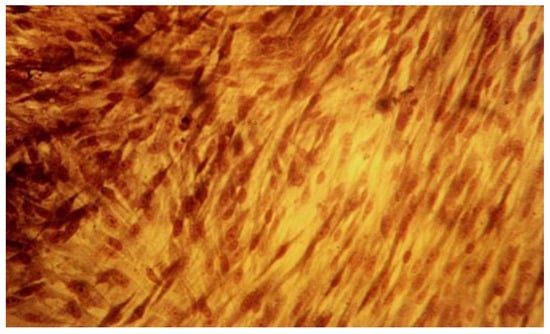

The qualitative expression of cytotoxicity was carried out microscopically and assessed by the cell cultures morphology analysis, reveals different degrees of cellular degeneration in contact with the investigated substances. We could observe different stages of membrane disintegration, nucleus changes and appearance of pathological pseudopodia.

Another specific aspect noted in this study is related to the appearance of the rounded cells detached form the monolayer, these being death or dying cells, as loss of adherence usually initiates apoptosis. The presence of dead cells is a result of pathological progression of cells alterations in contact with tested materials used in the study. They were floating in the suspension and their number increased during the entire experiment in the investigated lots as an indicator of the substances cytologic effect (Figure 5, Figure 6, Figure 7 and Figure 8).

The qualitative assessment of biological effect by microscopic examination of cellular appearance is consistent with values for the cellular dead rates and cellular density. Different changes in general cellular morphology, whose progressive evolution during the experiment, conducted to death cell, and detachment from substrate, have been observed. The observations indicate more obvious and visible aspects for MTA HP than BD and they have been presented descriptively. Nevertheless, the microscopic evaluations are in general more difficult to be precisely identified and must be always referred to the entire experiment and numerical data obtained. For MTA HP, more visible cell membrane integrity damages were observed, in association with a higher number of floating death cells. Loss of membrane integrity is a clear indicator for an unfavorable prognosis for cell survival [26]. For BD the morphological degenerative cell alterations were more discrete, and the presence of round detached cells less important. The rounded aspect is related to first sign of cellular injury, swelling, later followed by different nuclei and nucleoli alterations. No clear-cut delimitation between the healthy and affected cells were observed.

Figure 5. Fibroblasts cell line L929 at 24-hour mark, MTA Repair HP (Angelus, Brazil) lot, 20x magnification. Degenerative cytoplasmic and membrane alterations.